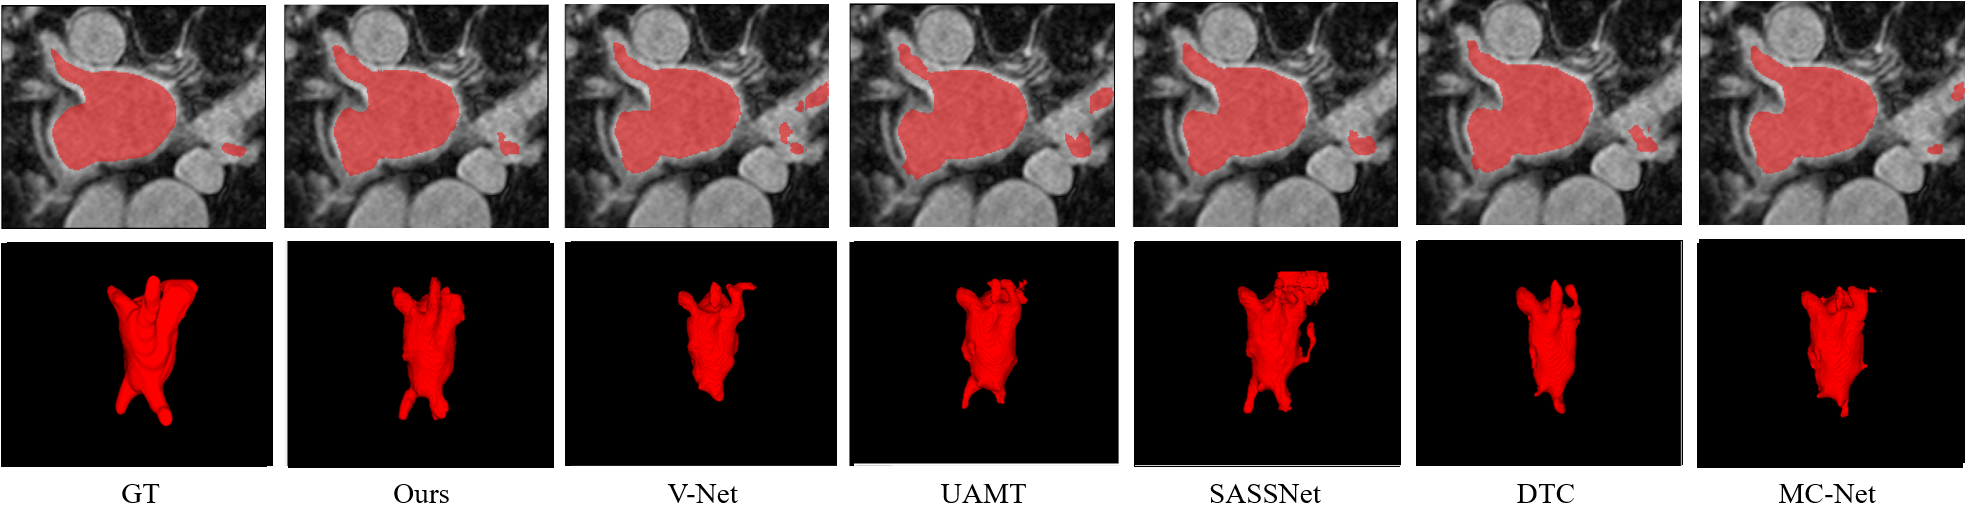

Left Atrial Segmentation Challenge dataset. We evaluated the performance of our proposed network in terms of its accuracy by comparing our results with those of the state-of-the-art models, i.e., domain-agnostic prior [33], UA-MT[10], SASSNet[13], local and global structure-aware entropy regularized mean teacher [34], double-uncertainty weighted method [35], DTC[11], contrastive voxel-wise representation learning [36], and MC-Net[12]. Two semi-supervised settings widely used on the LA dataset were available from a previous study [13] (i.e., using either 10 or 20% of the labeled data). Table I lists the quantitative results of LA segmentation. The results indicate that our proposed method achieves superior results in terms of the DSC, Jaccard index, and HD95 measurements and achieves competitive results on ASSD under the conditions of both 10% and 20% labeled data. Qualitative results are illustrated in Fig. 5. It can be observed that our method has a higher overlap ratio with respect to the ground truth in both 2D and 3D visualizations, thereby producing fewer false positives.

Abdominal multi-organ dataset To prove the effectiveness of our method on a multiclass dataset, we conducted an experiment on an MO dataset. For comparison, several state-of-the-art models (i.e., UA-MT[10], SASSNet[13], DTC[11], and MC-Net[12]) and the base network, VNet, were used for evaluation. We considered 20% of training data among the 70 images as the labeled data (14 labeled) and the others as unlabeled data (54 unlabeled). All the models used VNet as their backbone network. Table II presents quantitative comparisons of the segmentation results. The results indicate that our method outperforms the other methods in terms of all evaluation metrics (i.e., Dice (71.28%), Jaccard index (59.01%), HD (4.32), and ASSD (1.24)). Our method achieves significant improvements in the segmentation of spleen, liver, stomach, and pancreas and demonstrates competitive results for other organs. A box plot for a more precise quantitative comparison is presented in Fig. 4. The qualitative results illustrated in Fig. 6 indicate that our method segments multiple organs better than other methods.